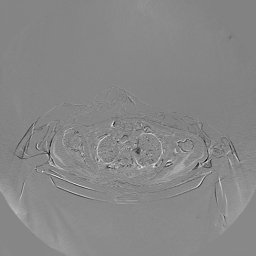

The experimental results on clinical head data are shown in Fig. 4. The reference images were reconstructed using the fast iterative shrinkage-thresholding algorithm (FISTA) with total variation regularization from non-truncated projection data. In the WCE reconstructions (Fig. 4(b)), severe truncation prevents accurate recovery of anatomical structures outside the FOV. Despite being trained solely on simulated data with a domain gap, all deep learning models can restore a substantial portion of the missing anatomy. Among them, the diffusion-based methods recover soft-tissue boundaries more faithfully than the conventional deep learning approach FBPConvNet, highlighting their stronger image generation capability. However, cDDPM reconstructions exhibit more noticeable noise than those from other methods, consistent with the simulated data results. The patchDiffusion model introduces artifacts within the FOV, likely due to its patch-wise processing strategy. While I2SB shares the same limitations as other diffusion models in perfectly restoring soft-tissue detail, it produces fewer residual noise patterns and fewer artifacts within the FOV boundaries. Overall, Fig. 4 demonstrates the strong efficacy of I2SB in reconstructing real CBCT data.